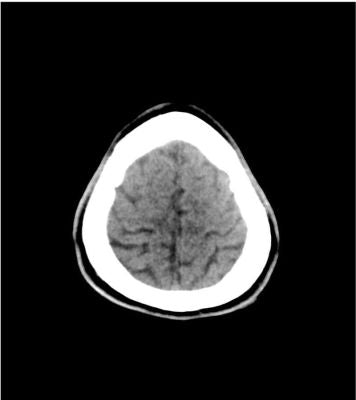

Description

This phantom simulates a head with stroke and bleeding patterns. It covers the vertex to the foramen magnum.

Stroke patterns include signs of early infarction (hyperdense middle cerebral artery, disappearing basal ganglia), acute and subacute watershed infarcts, and lacunar infarctions of varying ages.

Bleeding patterns include subarachnoid hemorrhage, subdural hemorrhage of varying ages, intraventricular hemorrhage, and intracerebral hemorrhage.

The phantom can be used in CT (including CBCT) to evaluate and optimize imaging performance and AI-enabled diagnosis.

It is also suited for training purposes. The phantom provides a detailed and realistic simulation of common brain pathologies, soft and bone tissues. Air voids are filled with a cellulose-polymer composite of approx. -160 HU.

Stroke:

• Hyperdense middle cerebral artery (MCA) and disappearing basal ganglia on the left side

• Watershed infarcts in middle/posterior(MCA/PCA) and anterior/middle cerebral artery (ACA/MCA) territories

• 8 lacunar infarcts of varying ages

Hemorrhage

• Subarachnoid hemorrhage (2 territories)

• Subdural hemorrhage of varying ages (3 territories)

• Intraventricular hemorrhage (left lateral ventricle)

• Intracerebral hemorrhage (2 thalamic, 6 subcortical)